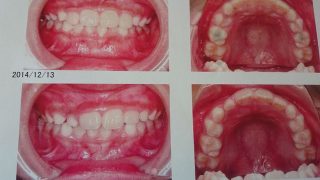

矯正歯科に行きました。二人とも少しずつよくなっています。《とり》は上の前歯四本につけていたワイヤーを外しました。